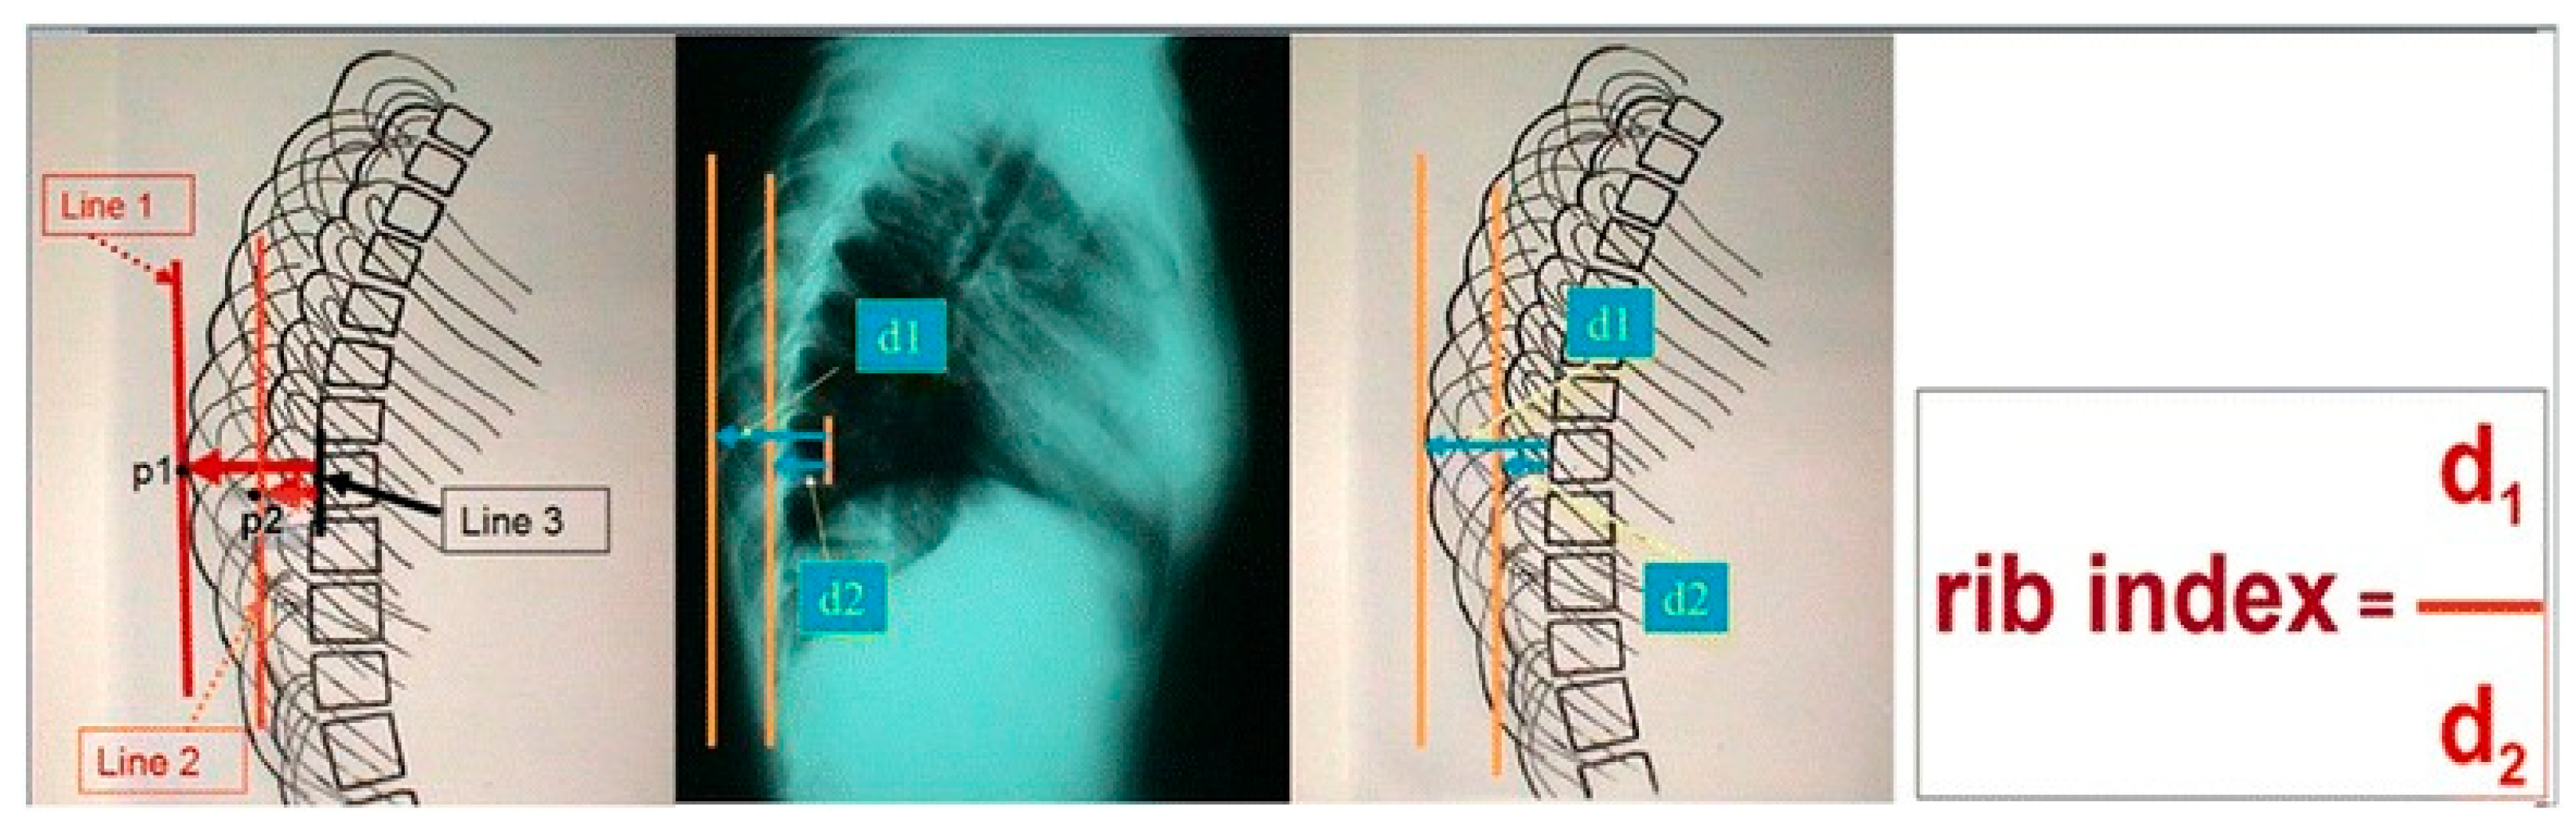

- Grivas TB. Rib index. Scoliosis. 2014, 9: 20. [CrossRef] [PubMed]